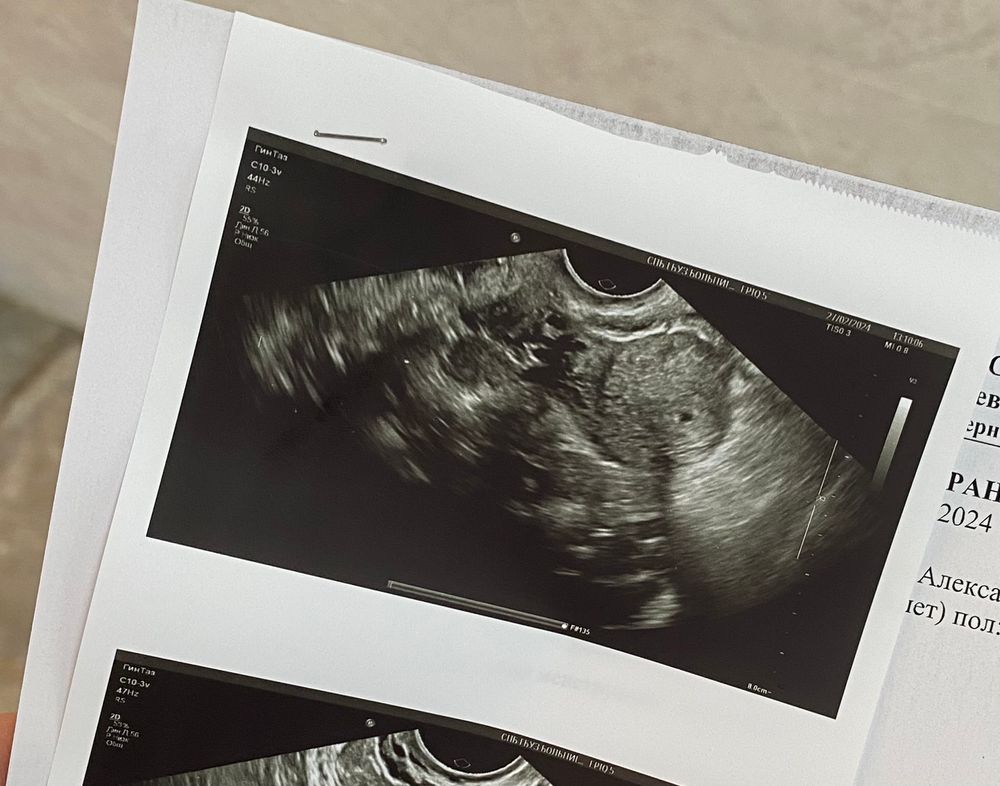

Фолликулометрия

Наше первое фото 🥰 19 дпо сегодня, размер пя 2,6 мм